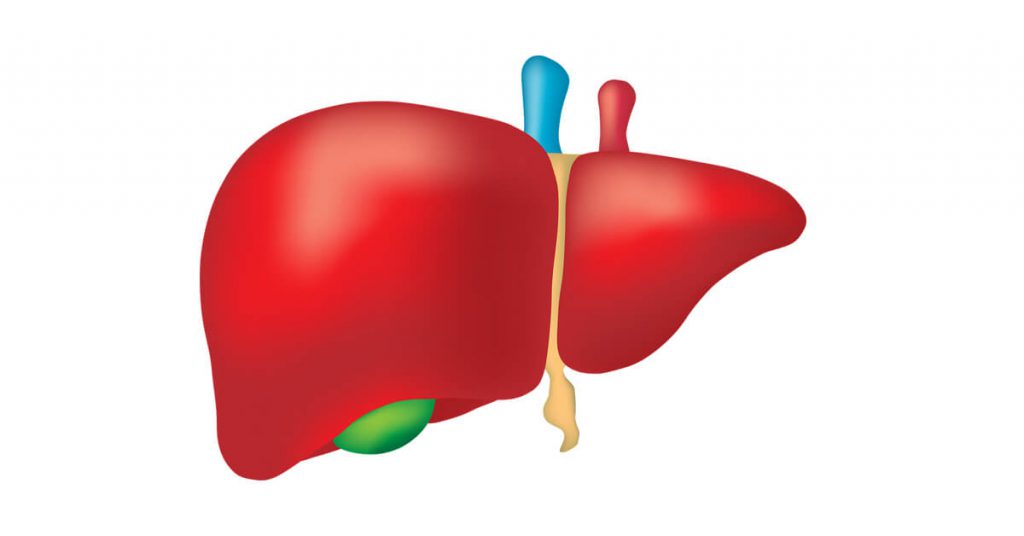

الكبد

.الوصف: أكبر غدة في الجسم، يقع في الجانب الأيمن العلوي من البطن

الوظائف

.إنتاج العصارة الصفراوية التي تساعد في هضم الدهون-

.تخزين السكر على شكل جليكوجين وتنظيم مستوياته في الدم-

.إزالة السموم من الدم وتصنيع البروتينات المهمة لتجلط الدم-